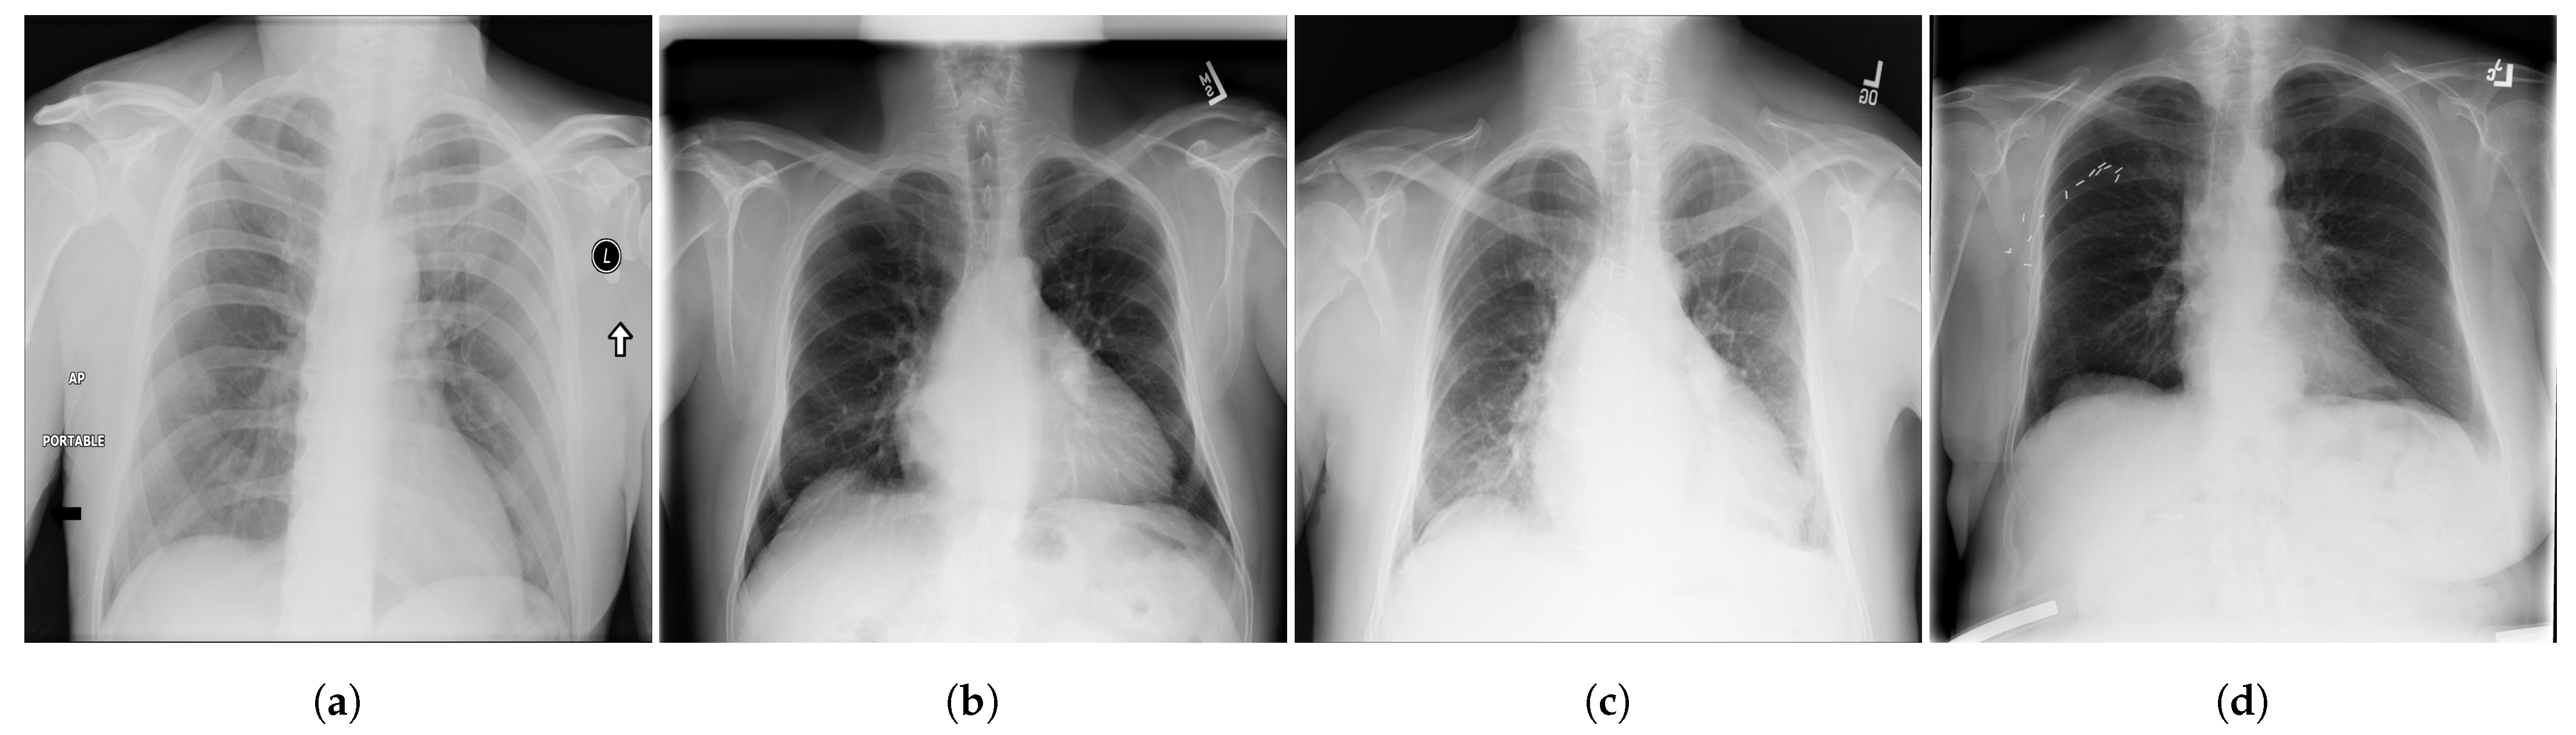

- ChestX-ray14 [39] is a dataset of images extracted from the PACS (Picture Archiving and Communication Systems) databases. It is an upgraded version of ChestX-ray8 dataset with six more common chest abnormalities (hernia, fibrosis, pleural thickening, consolidation, emphysema, and edema). ChestX-ray14 has 112,120 frontal view CXR images (51,708 images contain one or multiple abnormalities and the remaining 60,412 images do not include any of the 14 abnormalities) belonging to 30,805 unique patients. ChestX-ray14 was also labeled using NLP techniques. Examples of CXR images from ChestX-ray14 are depicted in Figure 2.

Figure 2.

Examples of CXR images from ChestX-ray14 dataset [39] where, (a) Nodule; (b) Emphysema; (c) Effusion; (d) Infiltration.